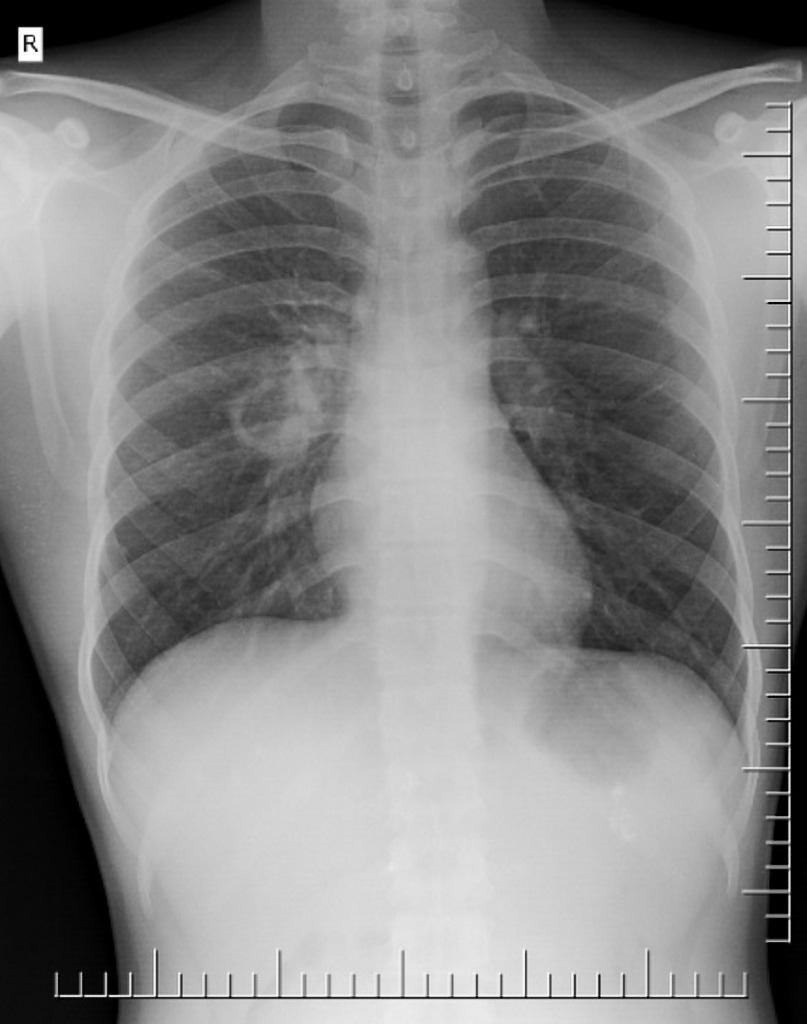

Comment on this CXR

A well defined thick walled cavitatory lesion is noted in the right para-hilar area in the midzone of right lung

aka Pulmonary TB